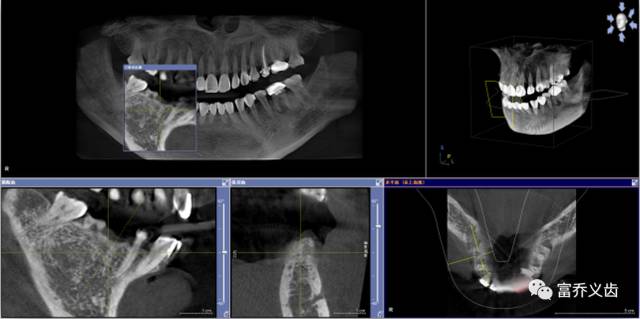

种植前曲面断层以及CBCT片